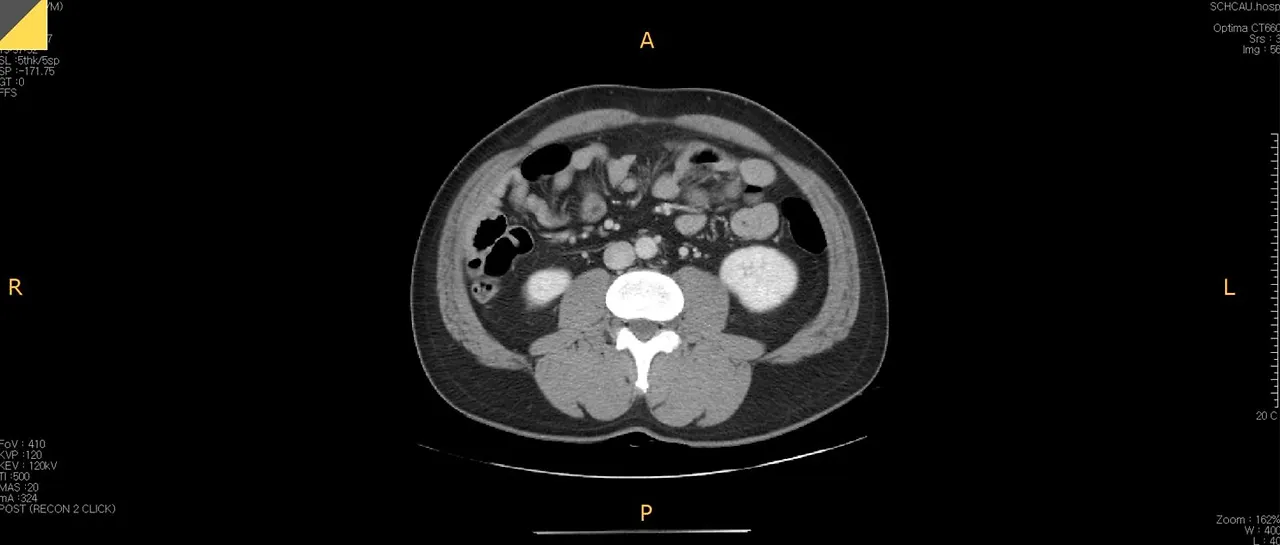

복부CT.JPG 언뜻 봐도 슬림해 보이지 않는 배뚱뚱이의 복부 CT 사진

시작부터 깜짝 놀랄 그림 하나 보여드리고 시작합니다. 이 사진은 배뚱뚱이가 지난 8월에 배탈이 나서 찍은 복부 CT 사진입니다. 언뜻 봐도 슬림해 보이진 않네요. 오늘의 주제는 바로 이 부분, 뱃살입니다.